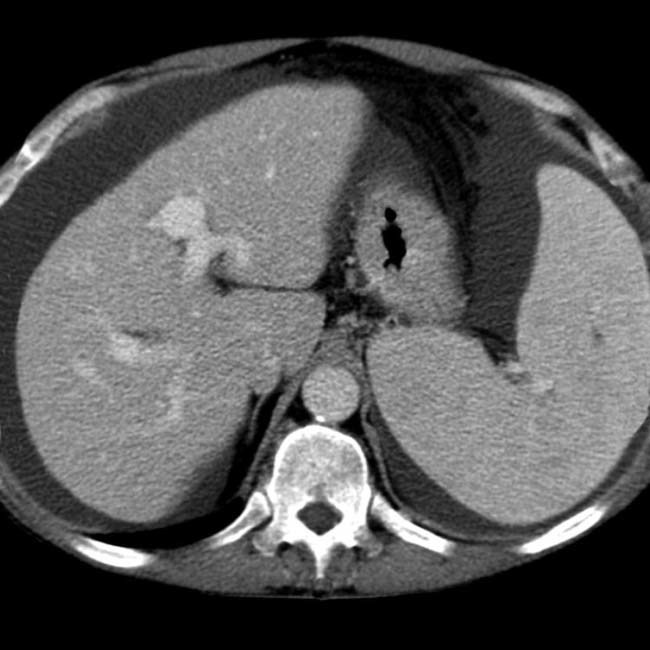

Triple phase CT scan

CT scan with IV contrast that acquires images at 30 seconds (arterial), 60 seconds (portal-venous), and 90 seconds (equilibrium)

Alows for better characterization of liver lesions

Types of focal liver lesion

Liver hemangioma

Focal nodular hyperplasia